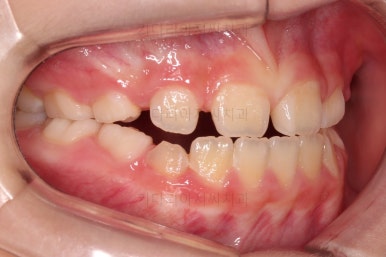

초진 시 입안의 모습입니다.

아래쪽 치열이 전반적으로 윗니보다 앞쪽에 위치한 전형적인 앵글씨 3급 부정교합인데요.

어금니에서부터 앞니까지 아랫니가 윗니보다 앞쪽에 위치하네요.

특히 앞니는 아랫니가 윗니보다 나와있는 "반대교합" 상태였고요.

또한 위아래로 겹침이 없고 떠있는 "개방교합" 상태였어요.

즉, 앵글씨 3급 부정교합 - 반대교합 - 개방교합 등 굉장히 복합적인 교합의 문제를 가진 환자였습니다.